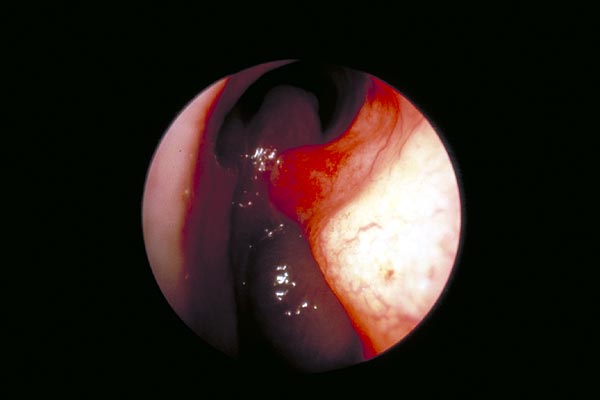

Zwischen dem Septum, links im Bild, und der unteren Nasenmuschel, rechts, sieht man gräulich-glänzende Polypen. Sie füllen das Nasenlumen vollständig aus.